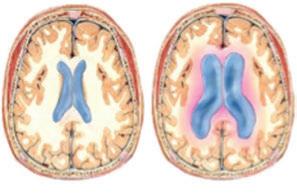

Ο εγκέφαλος περιέχει εκτός από το εγκεφαλικό παρέγχυμα και ανατομικές δομές που σχηματίζουν κοιλότητες και ονομάζονται κοιλίες του εγκεφάλου. Οι κοιλίες του εγκεφάλου είναι τέσσερις και περιέχουν το εγκεφαλονωτιαίο υγρό το οποίο παράγεται καθ’ όλη την διάρκεια του 24ώρου και παροχετεύεται προ της φλεβική κυκλοφορία. Η συνεχόμενη παραγωγή και παροχέτευση έχει σαν αποτέλεσμα την παραμονή σταθερής ποσότητας εγκεφαλονωτιαίου υγρού εντός των κοιλιών του εγκεφάλου (περίπου 150ml). Η παραγωγή του εγκεφαλονωτιαίου υγρού είναι περίπου στον ενήλικα 500ml το 24ώρο, δηλαδή ανανεώνεται τουλάχιστον τρεις φορές. Η διαταραχή στην σχέση μεταξύ παραγωγής και παροχέτευσης (μικρότερη), οδηγεί σε παραμονή μεγαλύτερης ποσότητας εγκεφαλονωτιαίου υγρού εντός των κοιλιών με τελικό αποτέλεσμα τον υδροκέφαλο. που αφορά συνήθως ασθενείς άνω των 60 ετών ονομάζεται υδροκέφαλος εκ φυσιολογικής πίεσης, διότι παρότι που αυξάνεται η ποσότητα του εγκεφαλονωτιαίου υγρού

εντός των κοιλιών δεν αυξάνεται υπέρμετρα η ενδοκοιλιακή πίεση. Η κλινική εικόνα των ασθενών με υδροκέφαλο εκ φυσιολογικής πίεσης είναι η κλασική τριάδα που αποτελείται από διαταραχή στην βάδιση (αστάθεια), διαταραχή στην ούρηση (ακράτεια) και διαταραχή στην μνήμη που όταν εξελιχθεί μπορεί να καταλήξει σε άνοια. Η διάγνωση της πάθησης γίνεται με την διενέργεια αξονικής ή μαγνητικής τομογραφίας εγκεφάλου και με μέτρηση της πίεσης του εγκεφαλονωτιαίου υγρού. Η νευροχειρουργική αντιμετώπιση του υδροκέφαλου εκ φυσιολογικής πίεσης πρέπει να γίνεται εγκαίρως με την τοποθέτηση κοιλιοπεριτοναϊκής παροχέτευσης (βαλβίδα υδροκεφάλου). Η βαλβίδα στην ουσία ρυθμίζει την ποσότητα του εγκεφαλονωτιαίου υγρού που παραμένει στο κοιλιακό σύστημα με τελικό αποτέλεσμα την εσωτερική αποσυμπίεση του εγκεφάλου. Η δεύτερη σε συχνότητα πάθηση που μπορεί να προκαλέσει υδροκέφαλο είναι σε περιπτώσεις που έχουμε απόφραξη της φυσιολογικής παροχέτευσης του εγκεφαλονωτιαίου υγρού από τον εγκέφαλο προς τους φλεβώδεις κόλπους και στην συνέχεια στην φλεβική αιματική ροή. Οι όγκοι του εγκεφάλου είτε είναι καλοήθεις είτε είναι κακοήθεις μπορούν να προκαλέσουν απόφραξη και να εμφανίσουν οι ασθενείς την κλινική του υδροκεφάλου. Οι πιο συχνοί είναι οι όγκοι που εμφανίζονται στον οπίσθιο κρανιακό βόθρο δηλαδή την παρεγκεφαλίδα. Στην περίπτωση των όγκων του εγκεφάλου η θεραπεία είναι χειρουργική και αποσκοπεί στην ολική αφαίρεση του όγκου. Μετά την αφαίρεση του όγκου, αποκαθίσταται η φυσιολογική παροχέτευση του εγκεφαλονωτιαίου υγρού και τις περισσότερες φορές δεν χρειάζεται η τοποθέτηση βαλβίδας υδροκεφάλου. Υπάρχουν δύο μεγάλες

χωρίς να χρειάζεται επιπλέον θεραπείες. Μετεγχειρητικά γίνεται κλινική επανεξέταση του ασθενούς και διενέργεια αξονικής τομογραφίας. Η αντιμετώπιση παθήσεων όπως ο υδροκέφαλος εκ φυσιολογικής πίεσης απαιτεί μια μικρή επέμβαση που θα πρέπει να γίνεται εγκαίρως, πριν δημιουργηθούν μόνιμες βλάβες στον εγκέφαλο. ΤΑΧΥΔΡΟΜΟΣ Υδροκέφαλος­-­Αντιμετώπιση Γράφει ο­­Μπρίζας Στέργιος, Διευθυντής­Β΄­Νευροχειρουργικήςκλινικής,­ΙΑΣΩ­Θεσσαλίας Διάταση του κοιλιακού συστήματος (υδροκέφαλος) Μηχανισμός βαλβίδας υδροκεφάλου Διάφοροι τύποι όγκων παρεγκεφαλίδας που μπορεί να προκαλέσουν υδροκέφαλο Διάταση του κοιλιακού συστήματος (υδροκέφαλος)